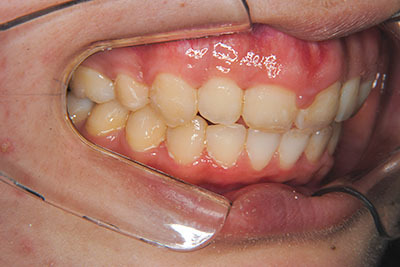

おとなの方でも矯正治療をあきらめないでください!

子供の頃に矯正治療を行う方が治療期間が短く済むというのは、確かですが、矯正治療は患者様の意識も重要です。

いくら歯が動き易くとも、本人がやる気でなければ効果は出ませんし、むし歯発生のリスクも高まります。おとなの方は顎の成長が終わっているため、治療の計画が立てやすいとも言えます。「もう大人だから…」とあきらめず、一度ご相談ください。